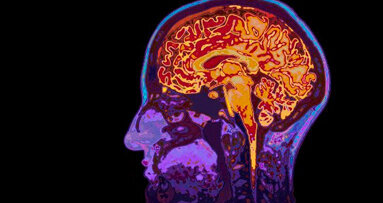

I ricercatori del dentale della New York University hanno trovato la prima prova di lungo termine che la malattia parodontale (gum) può aumentare il rischio di disfunzione cognitiva associata a morbo di Alzheimer in individui sani e in coloro che già sono propensi a deterioramento cognitivo.

Lo studio della NYU offre nuove prove sul fatto che l’infiammazione delle gengive possa contribuire anche a un’infiammazione cerebrale, alla neurodegenerazione e all’Alzheimer.

Il gruppo di ricerca, guidato dalla dottoressa Angela Kamer, assistant professor di Parodontologia e Implantologia, ha esaminato 20 anni di dati che supportano l’ipotesi di un possibile nesso di causalità tra malattia parodontale e morbo di Alzheimer.

“La ricerca suggerisce che i soggetti cognitivamente normali, con infiammazione parodontale, sono inclini a un rischio amplificato di abbassamento delle funzioni cognitive rispetto ai soggetti cognitivamente normali, con poca o nessuna infiammazione parodontale”, ha detto la d.ssa Kamer.

La ricerca della d.ssa Kamer, condotta in collaborazione con il dr. Douglas E. Morse, professore associato di Epidemiologia e Promozione della Salute alla New York University College of Dentistry, e con un team di ricercatori danesi, si basa su uno studio del 2008 della Kamer che ha trovato che i soggetti con morbo di Alzheimer avevano un livello significativamente più alto di anticorpi e molecole infiammatorie nel plasma, associate a malattia parodontale, rispetto a persone sane.

Gli ultimi risultati di questo studio sono basati su un’analisi dei dati sull’infiammazione parodontale e sulle funzioni cognitive in 152 soggetti all’interno del Glostrop Aging Study: sono stati raccolti dati medici, psicologici, odontoiatrici e dati sociali su uomini e donne danesi. La d.ssa Kamer ha valutato che i dati coprono un periodo di 20 mesi fino al 1984, quando i soggetti avevano tutti raggiunto i 70 anni di età. I risultati sono stati presentati dalla Kamer in occasione della riunione annuale del 2010 dell’International Association for Dental Research a Barcellona, Spagna.